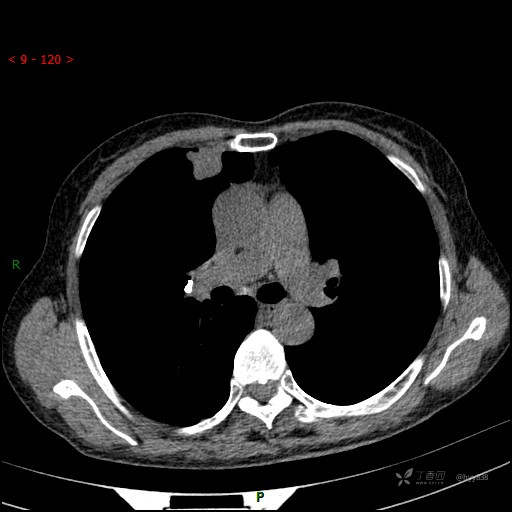

静脉期

CT值